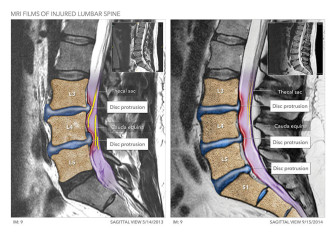

Lumbar Spine Decompression Surgery

Available in high resolution JPEG or PDF formats, 8x10 print, or laminated foam core exhibit board (24x46, 30x40 or 36x48).